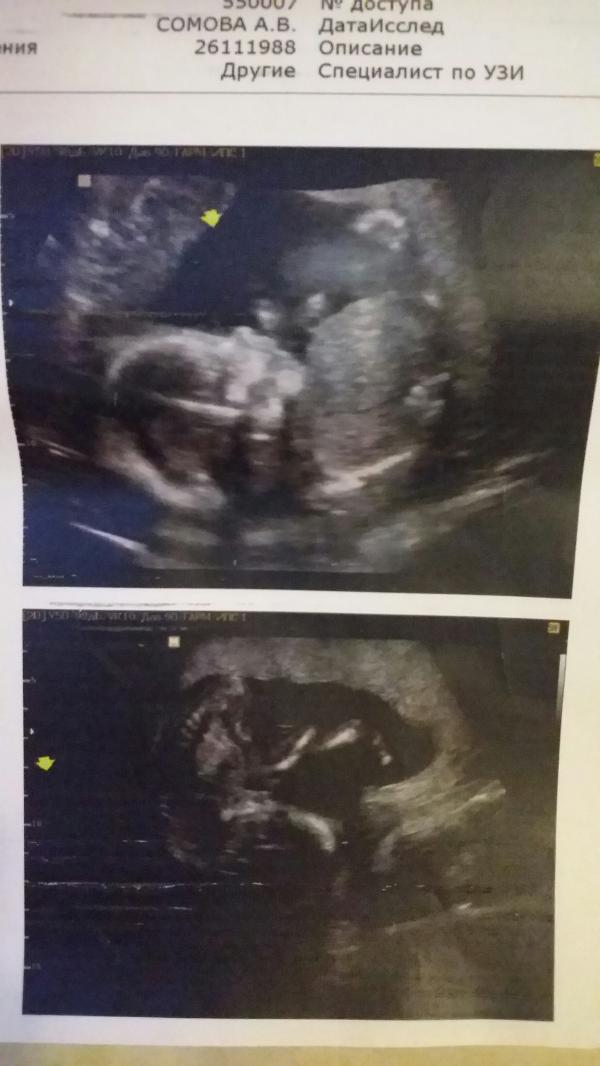

Спасибо всем, кто посоветовал Нагоеву. Очень подробно все показала, рассказала. Даже носик замерила😄

Показала две полосочки и сказала - сто процентная девочка 👯

Моя обезьянка 🙉